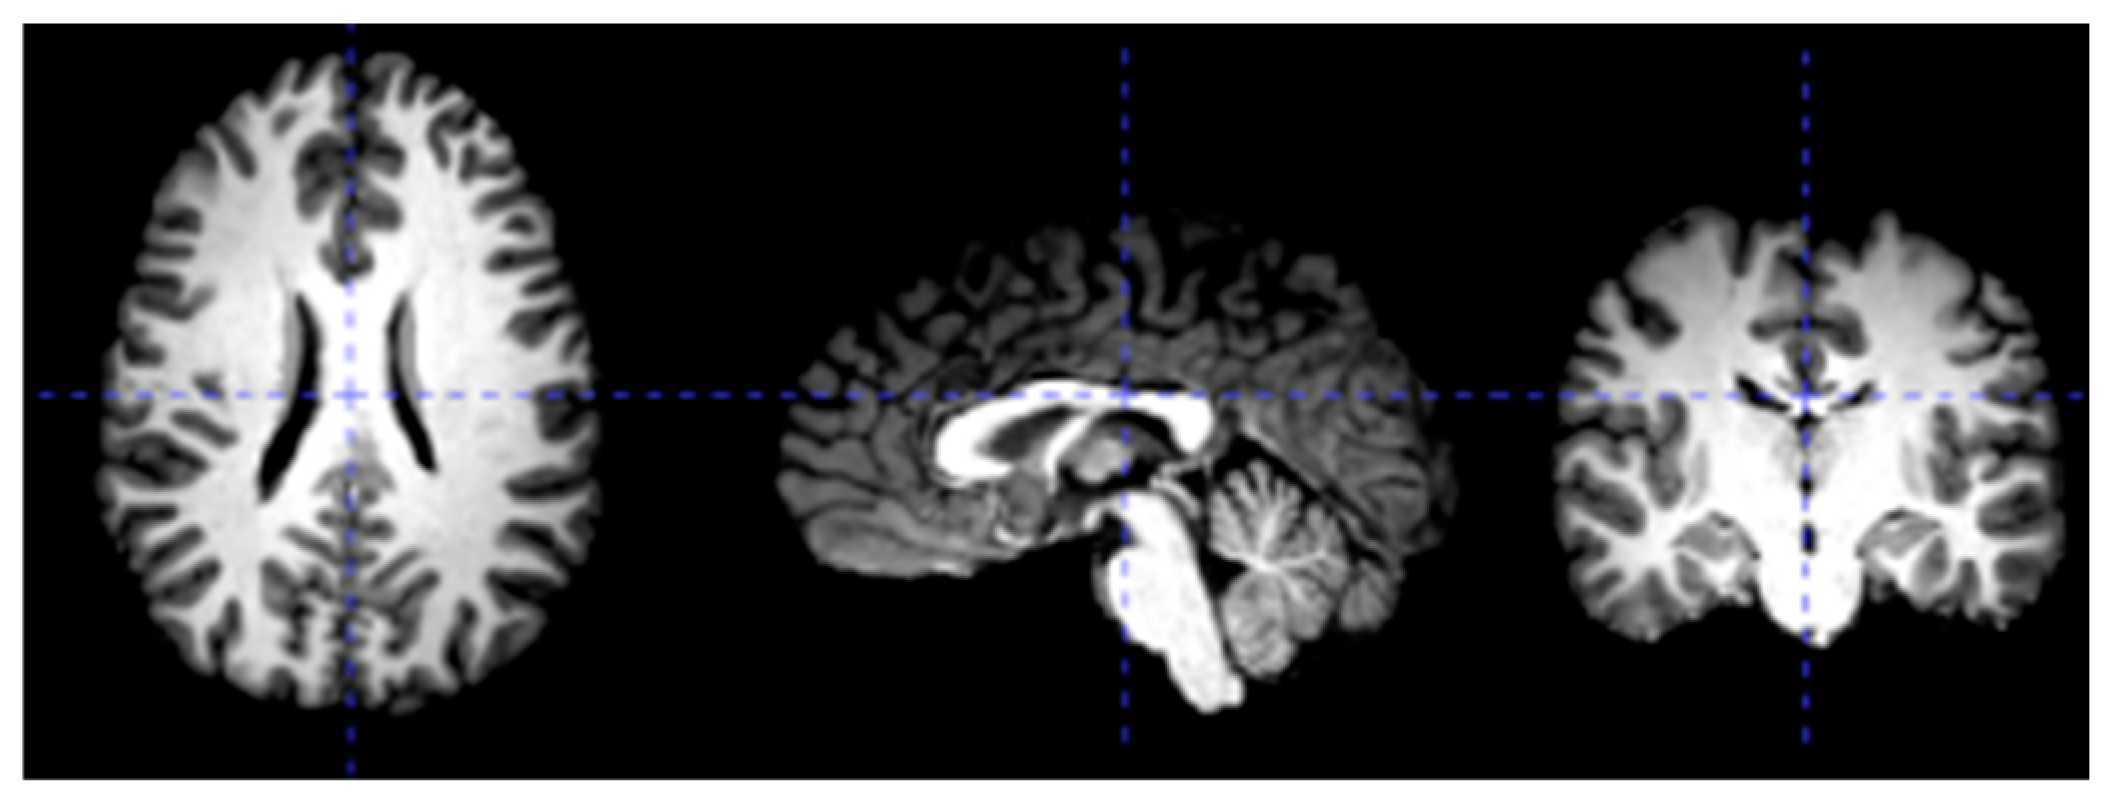

3.2. Data Preprocessing